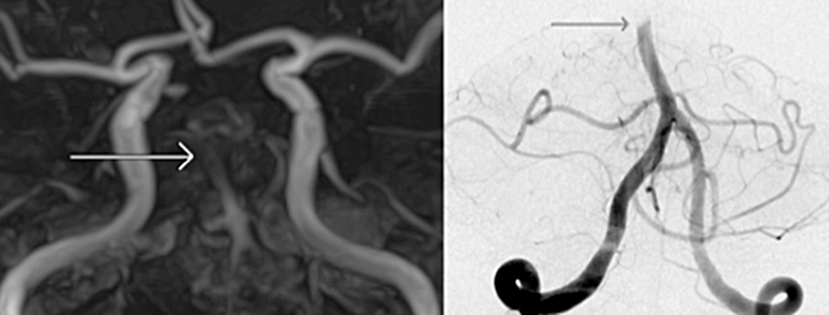

一つは“ステント”と呼ばれる金網を用いる方法、もう一つは“吸引カテーテル”と呼ばれる、文字通り血栓を吸引して除去する方法があります。

ステントは心筋梗塞や狭心症の時に細くなった心臓の血管を広げる時に使われているものとして知られております。ただ、血栓回収療法の時は少し違った使い方をします。血栓で詰まったところでステントを広げると、ステントが広がり血栓を押しつぶします。すると一時的に脳の血流が再開します。ただ、このまま様子をみるとステントの金網の中に血栓がめり込みます。そのうちめり込んだ血栓により再度血管が詰まってしまいます。これでは意味が無いのでは、と思ってしまいますが、再度詰まることでステントが血栓に絡んだと判断できます。そうすれば、このステントをゆっくり引くとステントに絡んだ血栓も一緒に引けて来て、ステントを抜去すると血栓も取り除くことができます。うまくいけば、1回で詰まった血栓を除去できます。